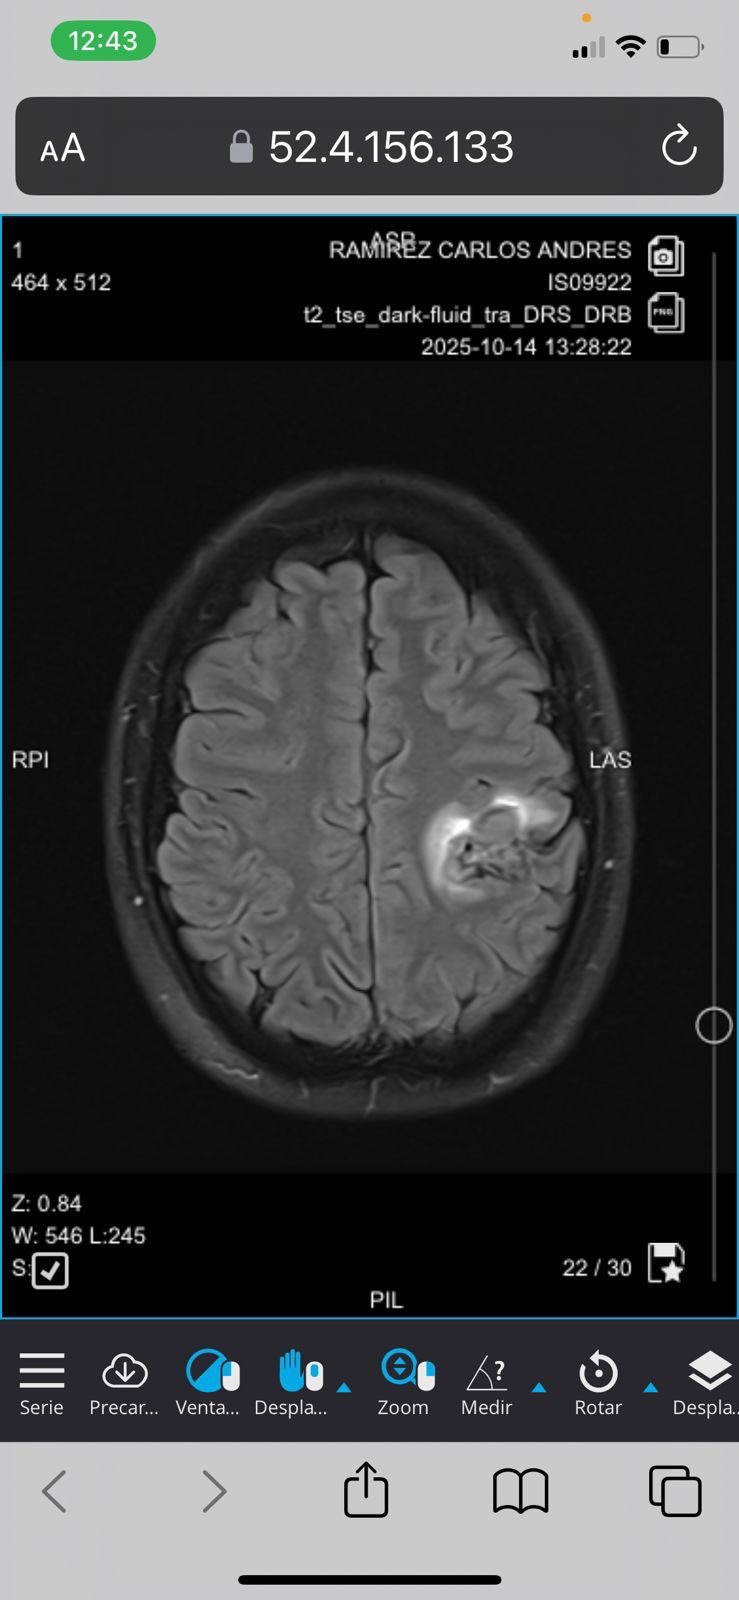

Hoy, lamentablemente, Carlos enfrenta una de las pruebas más difíciles de su vida. Fue diagnosticado con una hemorragia cerebral, una condición grave que avanza rápidamente y requiere una cirugía urgente para salvar su vida.

Today, Carlos is facing one of the toughest battles of his life. He was recently diagnosed with a brain hemorrhage, a serious and rapidly progressing condition that requires urgent surgery to save his life.